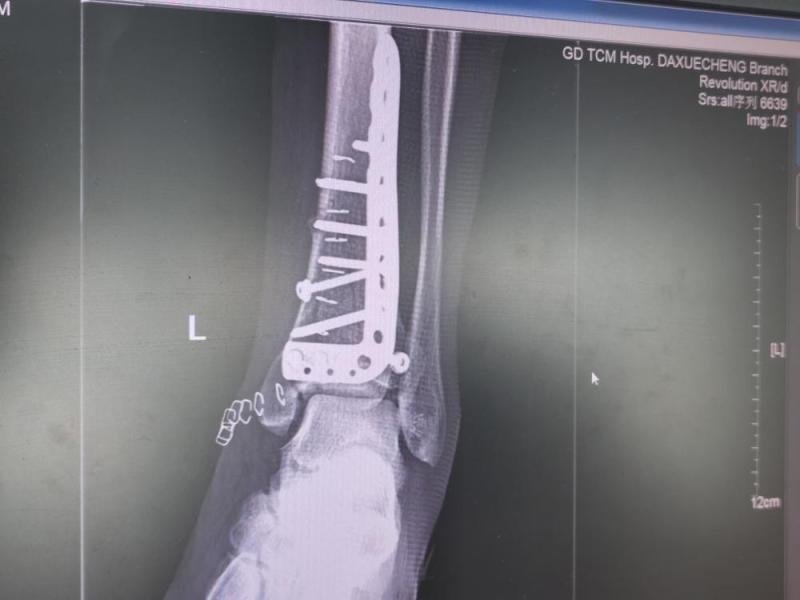

八月十二号回廉江老家,搞卫生,竹梯滑倒,跟着滑倒,腰椎第三节、左脚踝粉碎性骨折,17号做腰椎手术,25号做脚手术。Screenshot_20211119_071742_com.huawei.himovie.jpgScreenshot_20211119_071901_com.huawei.himovie.jpgScreenshot_20211119_071946.jpgScreenshot_20211119_071912_com.huawei.himovie.jpg